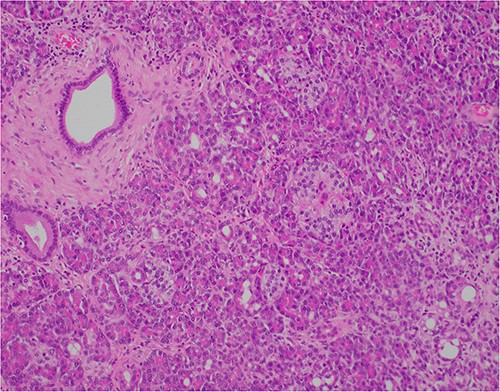

At outpatient phone clinic review 2 months post-surgery, the patient had recovered well, and his pre-operative symptoms of nausea, vomiting and pain had completely resolved. The histopathology of the gallbladder found chronic cholecystitis with cholelithiasis, in addition to a 6 mm focus of pancreatic heterotopia in the gallbladder wall. This heterotopic tissue contained acini, ducts and islet cells, classifying it as Type I pancreatic heterotopia (Figs 1–3).

×2 objective lens; low-magnification photograph showing an area of pancreatic heterotopia.

×10 objective lens; showing central duct with surrounding pancreatic acini and islets, with preserved architecture.

×20 objective lens; normal duct towards left hand side; acini (with dense pink cytoplasmic granules) and islets (clusters of pale cells).